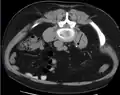

Imaging studies

Calcium-containing stones are relatively radiodense, and they can often be detected by a traditional radiograph of the abdomen that includes the kidneys, ureters, and bladder (KUB film).[58] KUB radiograph, although useful in monitoring size of stone or passage of stone in stone formers, might not be useful in the acute setting due to low sensitivity.[59] Some 60% of all renal stones are radiopaque.[60][61] In general, calcium phosphate stones have the greatest density, followed by calcium oxalate and magnesium ammonium phosphate stones. Cystine calculi are only faintly radiodense, while uric acid stones are usually entirely radiolucent.[62]

In people with a history of stones, those who are less than 50 years of age and are presenting with the symptoms of stones without any concerning signs do not require helical CT scan imaging.[63] A CT scan is also not typically recommended in children.[64]

Otherwise a noncontrast helical CT scan with 5 millimeters (0.2 in) sections is the diagnostic method to use to detect kidney stones and confirm the diagnosis of kidney stone disease.[16][56][60][65][7] Near all stones are detectable on CT scans with the exception of those composed of certain drug residues in the urine,[58] such as from indinavir.

Where a CT scan is unavailable, an intravenous pyelogram may be performed to help confirm the diagnosis of urolithiasis. This involves intravenous injection of a contrast agent followed by a KUB film. Uroliths present in the kidneys, ureters, or bladder may be better defined by the use of this contrast agent. Stones can also be detected by a retrograde pyelogram, where a similar contrast agent is injected directly into the distal ostium of the ureter (where the ureter terminates as it enters the bladder).[60]

Renal ultrasonography can sometimes be useful, because it gives details about the presence of hydronephrosis, suggesting that the stone is blocking the outflow of urine.[58] Radiolucent stones, which do not appear on KUB, may show up on ultrasound imaging studies. Other advantages of renal ultrasonography include its low cost and absence of radiation exposure. Ultrasound imaging is useful for detecting stones in situations where X-rays or CT scans are discouraged, such as in children or pregnant women.[66] Despite these advantages, renal ultrasonography in 2009 was not considered a substitute for noncontrast helical CT scan in the initial diagnostic evaluation of urolithiasis.[65] The main reason for this is that, compared with CT, renal ultrasonography more often fails to detect small stones (especially ureteral stones) and other serious disorders that could be causing the symptoms.[14]

On the contrary, a 2014 study suggested that ultrasonography should be used as the initial diagnostic imaging test, with further imaging studies be performed at the discretion of the physician on the basis of clinical judgment, and using ultrasonography rather than CT as an initial diagnostic test results in less radiation exposure and equally good outcome.[67]

Bilateral kidney stones can be seen on this KUB radiograph. There are phleboliths in the pelvis, which can be misinterpreted as bladder stones.

Bilateral kidney stones can be seen on this KUB radiograph. There are phleboliths in the pelvis, which can be misinterpreted as bladder stones.

Renal ultrasonograph of a stone located at the pyeloureteric junction with accompanying hydronephrosis.

Renal ultrasonograph of a stone located at the pyeloureteric junction with accompanying hydronephrosis. Measurement of a 5.6 mm large kidney stone in soft tissue versus skeletal CT window.

Measurement of a 5.6 mm large kidney stone in soft tissue versus skeletal CT window.